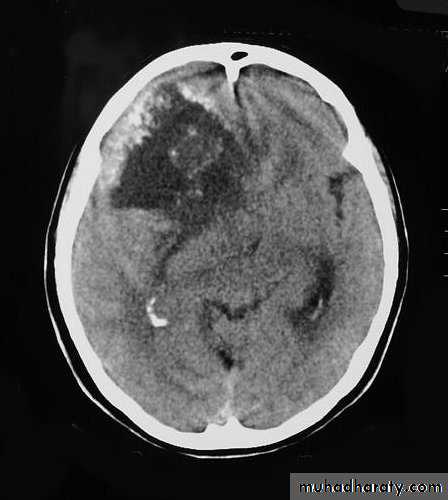

Malignant GliomaPre contrast CT

Neurosurgery

Malignant Glioma Post contrast CT